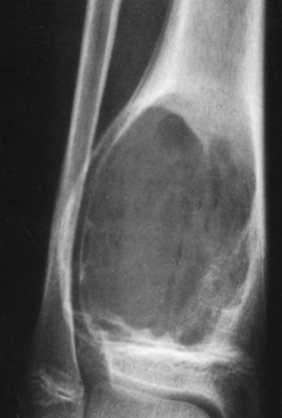

▌膨胀性破坏

膨胀性破坏是地图样破坏的特殊形式,影像学表现为骨质破坏区骨膨胀,周围可见不同程度扩张的骨壳(图 5、图 6、图 7、图 8)。膨胀性破坏是由于肿瘤从骨皮质内面破坏,骨外膜增生形成新生骨造成膨胀的。引起膨胀性破坏见于大多数良性肿瘤和肿瘤样病变如单纯性骨囊肿,动脉瘤样骨囊肿、内生软骨瘤和软骨粘液纤维瘤等,少数也可见于恶性肿瘤如转移瘤、骨髓瘤等。

图 6.膨胀性破坏:骨巨细胞瘤